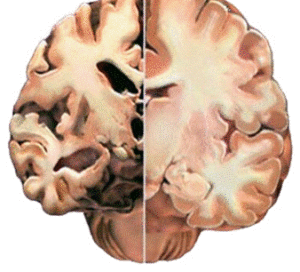

A livello Cerebrale l’immagine che segue parla da sola, a mostrare le conseguenze dell’abuso di sostanze stupefacenti. L’emisfero a sinistra è del cervello di una persona che fa uso di droghe: la corteccia si assottiglia, le sostanza bianca delle connessioni nervose si dirada, il cervello si atrofizza in maniera irreversibile dando il via al processo della demenza precoce, ma questa è un’altra storia.